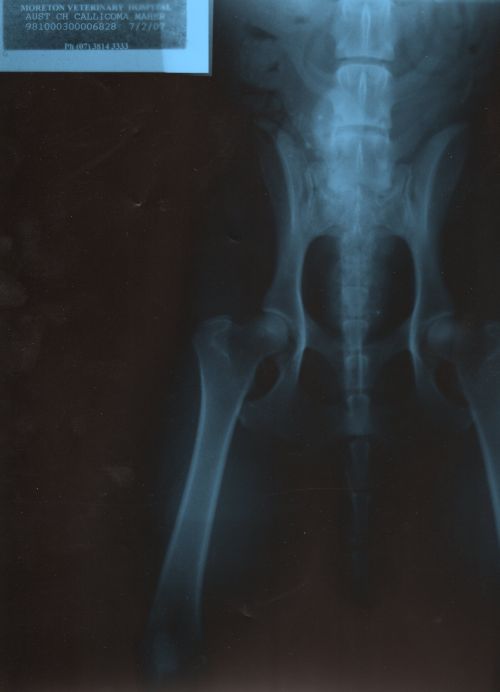

Tacker har Internationellt grad A, bedömt i Australien. Den bilden var väl bättre än den vi fick då.